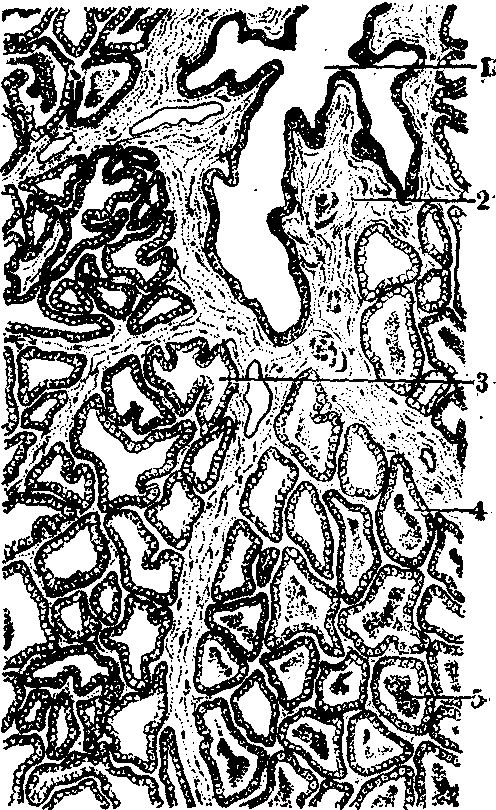

授乳期乳腺 授乳期乳腺的结构与妊娠期乳腺基本相似,但腺体更为发达,结缔组织更少。小叶内可见处于不同分泌时期的腺泡(图2)。有的腺泡细胞呈高柱状,胞质内富含分泌颗粒、粗面内质网和线粒体等,腺细胞处于分泌状态。有的腺泡处于分泌后状态,细胞呈立方或扁平形,腺泡腔中充满乳汁。乳汁中含有大量蛋白质、糖、脂肪和无机盐。

图2 授乳期乳腺

1.小叶间导管 2.小叶间结缔组织 3.分泌前的腺泡 4.分泌后的腺泡 5.乳汁